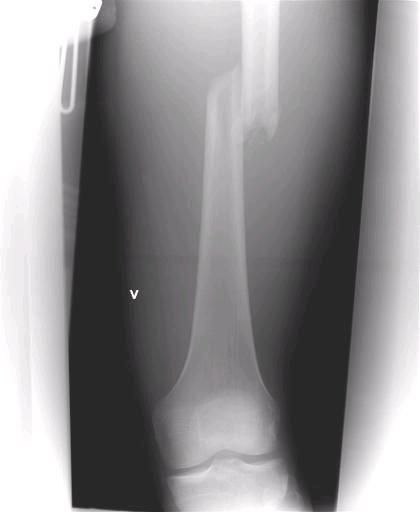

Lårbens brudd

Sentralsykehuset i førde

Erlend Reime

etter Stryn (

Stryn sommerski

)